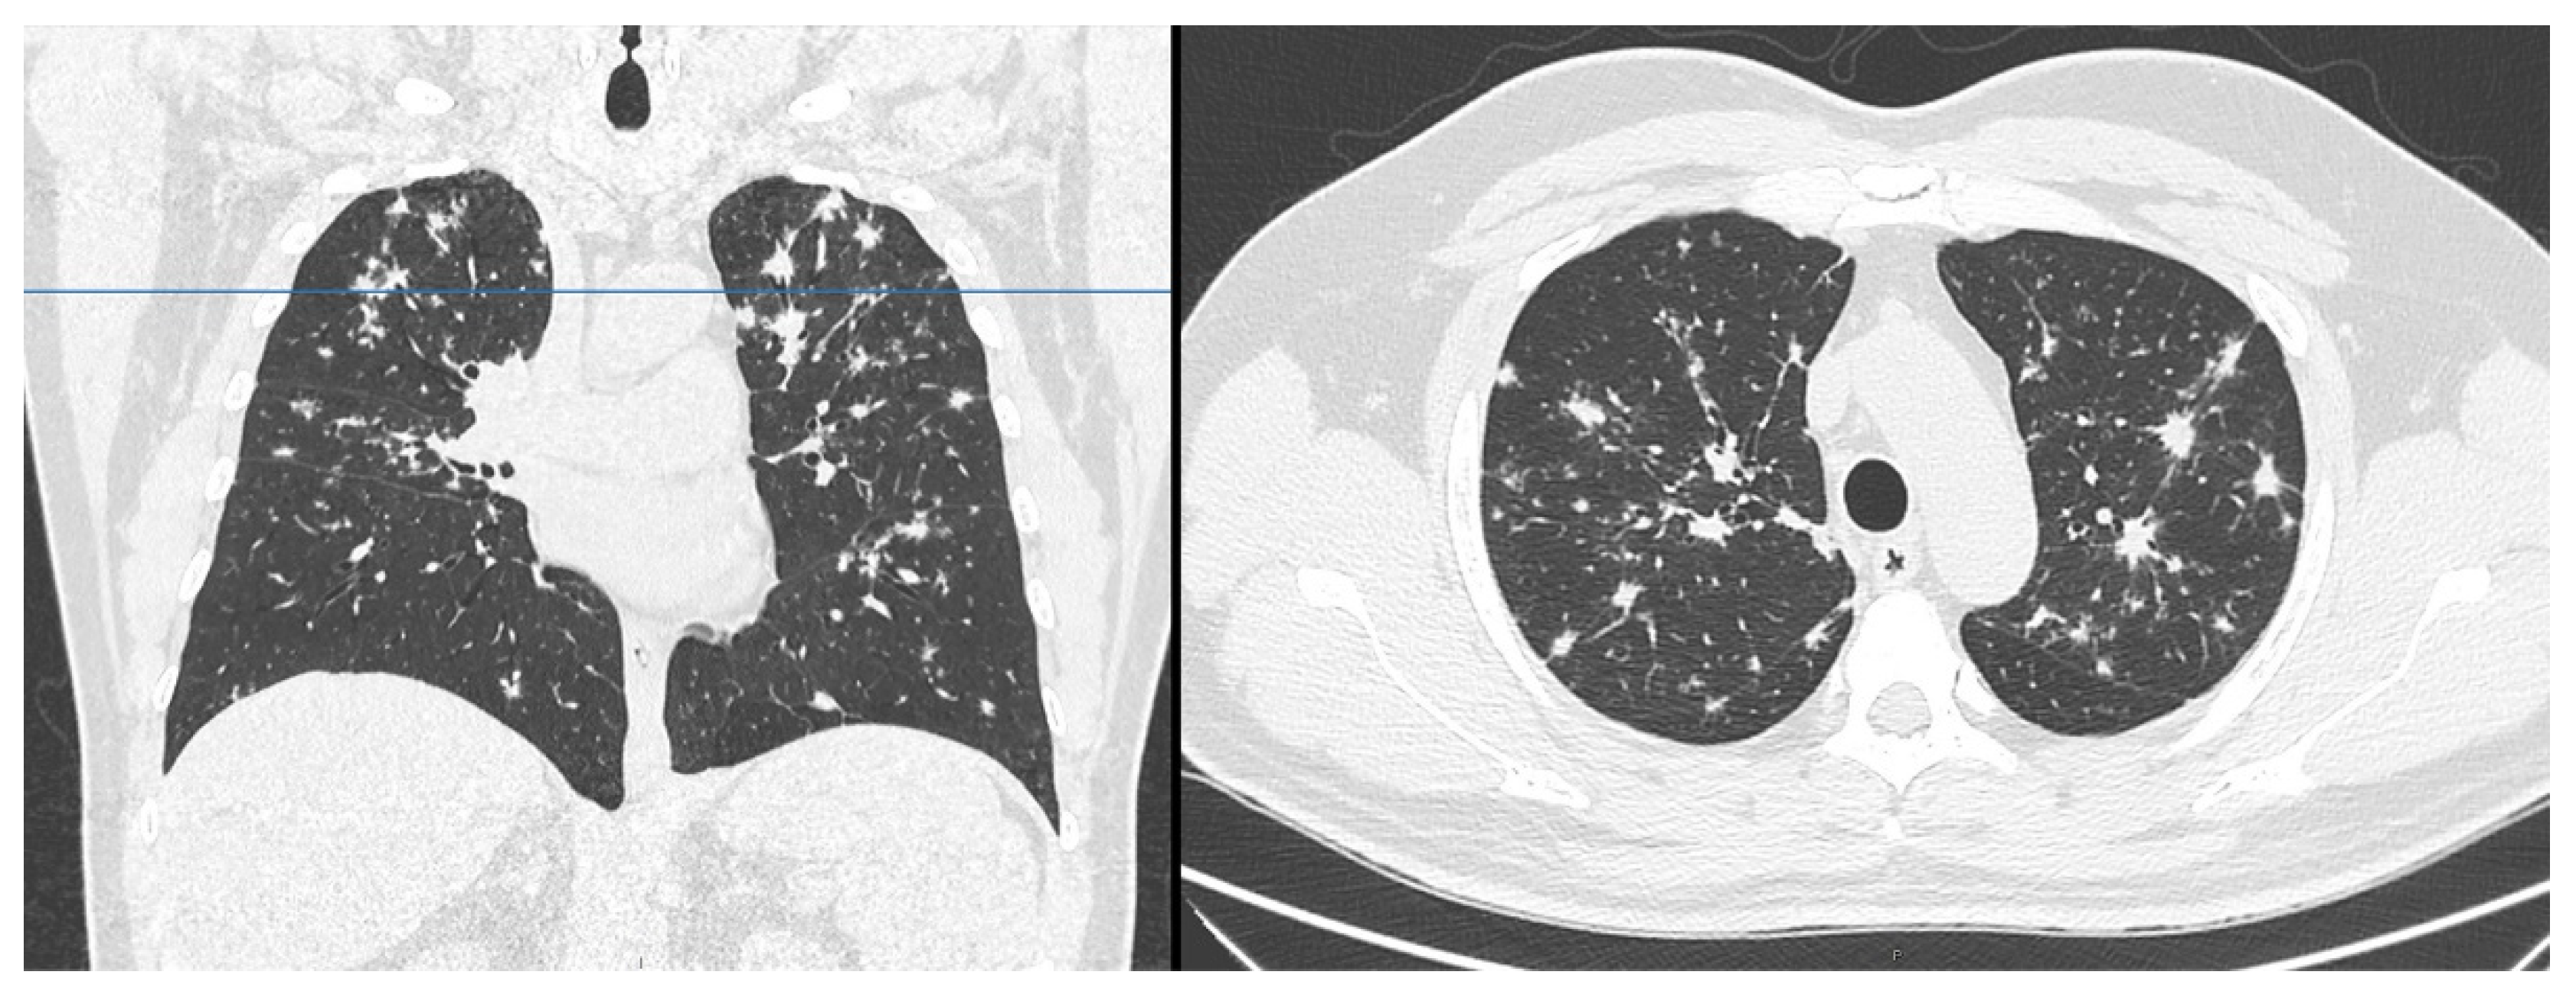

Figure 1.

Chest computed tomography showed multiple peribronchovascular nodules, mainly located in the upper lobes.